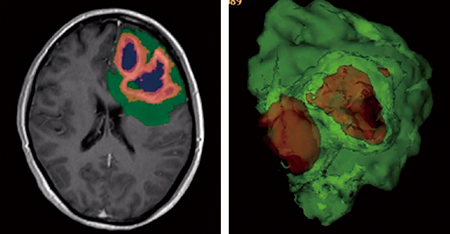

BraTS Challengeの220人分の造影前後のT1W,T2W,FLAIR画像を教師データに用いて,DeepMedic2)をベースにディープラーニングモデル開発を行った。ディープラーニングの課題の一つとして,学習用データを取得した施設においては高精度であるが,異なるデータセットでは精度が変わりうる。そこで本研究では,マルチセンタートライアルとして,15施設,ベンダー・磁場強度が混在した8種類のMRI装置,撮像条件(プロトコール)に幅を持たせた64例のデータでディープラーニングモデルの評価を行った(図1)。ディープラーニングモデルによるセグメンテーション結果は,医師によるセグメンテーションを参照にDICEスコアを用いて評価した。

図1 ディープラーニングによるGBMセグメンテーション

DICEスコアは,whole tumor(0.86±0.09),contrast enhance tumor(0.78±0.15),necrosis(0.62±0.30)であった。マルチセンタートライアルでは,ディープラーニングモデルが高精度でGBMのセグメンテーションが可能であることを示している。